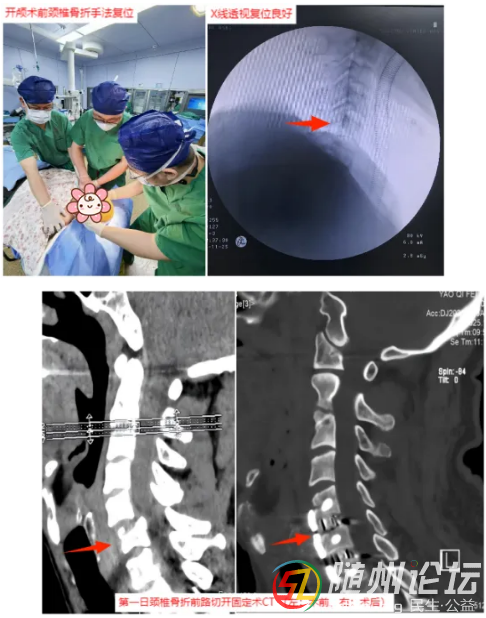

隨即,搶救團隊爭分奪秒。脊柱外科團隊首先對頸椎進行手法復(fù)位,為后續(xù)手術(shù)創(chuàng)造條件;隨后,神經(jīng)外科團隊立即進行開顱手術(shù),精準清除腦內(nèi)血腫,妥善處理出血點,并將碎裂的顱骨修復(fù)還原;鑒于頸椎骨折仍需穩(wěn)固內(nèi)固定以最大限度保護脊髓功能,緊接著,脊柱外科團隊再次手術(shù),對頸椎進行內(nèi)固定,穩(wěn)定骨折部位,解除對脊髓的壓迫。整個救治過程環(huán)環(huán)相扣,緊張有序。